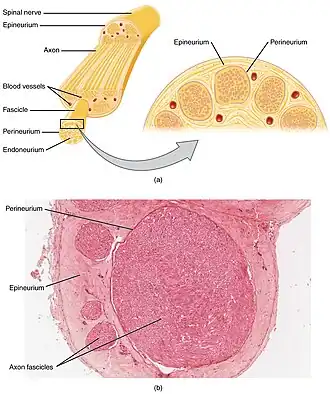

Cross-section of a nerve | |

Each axon is surrounded by a layer of connective tissue called the endoneurium. The axons are bundled together into groups called fascicles, and each fascicle is wrapped in a layer of connective tissue called the perineurium. The entire nerve is wrapped in a layer of connective tissue called the epineurium. Nerve cells (often called neurons) are further classified as either sensory or motor.

Each nerve is covered on the outside by a dense sheath of connective tissue, the epineurium. Beneath this is a layer of fat cells, the perineurium, which forms a complete sleeve around a bundle of axons. Perineurial septa extend into the nerve and subdivide it into several bundles of fibres. Surrounding each such fibre is the endoneurium. This forms an unbroken tube from the surface of the spinal cord to the level where the axon synapses with its muscle fibres, or ends in sensory receptors. The endoneurium consists of an inner sleeve of material called the glycocalyx and an outer delicate meshwork of collagen fibres.[2] Nerves are bundled and often travel along with blood vessels, since the neurons of a nerve have fairly high energy requirements.